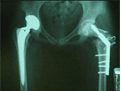

수술후 사진

수술 후 사진

우측고관절은 병이 많이 진행하여 인공고관절치환술로 치료하였고,좌측고관절은 대퇴전자간 회전 절골술로 치료하였음. 대퇴골두상부의 함몰된 부분이 아래로 이동되었고, 체중부하 부위인 상부는 괴사가 없는 정상골로 대치되었음.